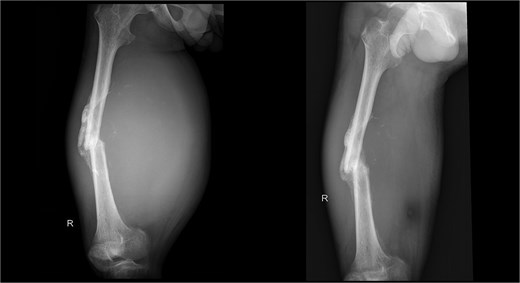

X-ray imaging of the right femur reveals a mid-shaft fracture with prominent callus formation. A soft tissue mass is observed surrounding the right femur, with no evidence of underlying bone lesions.